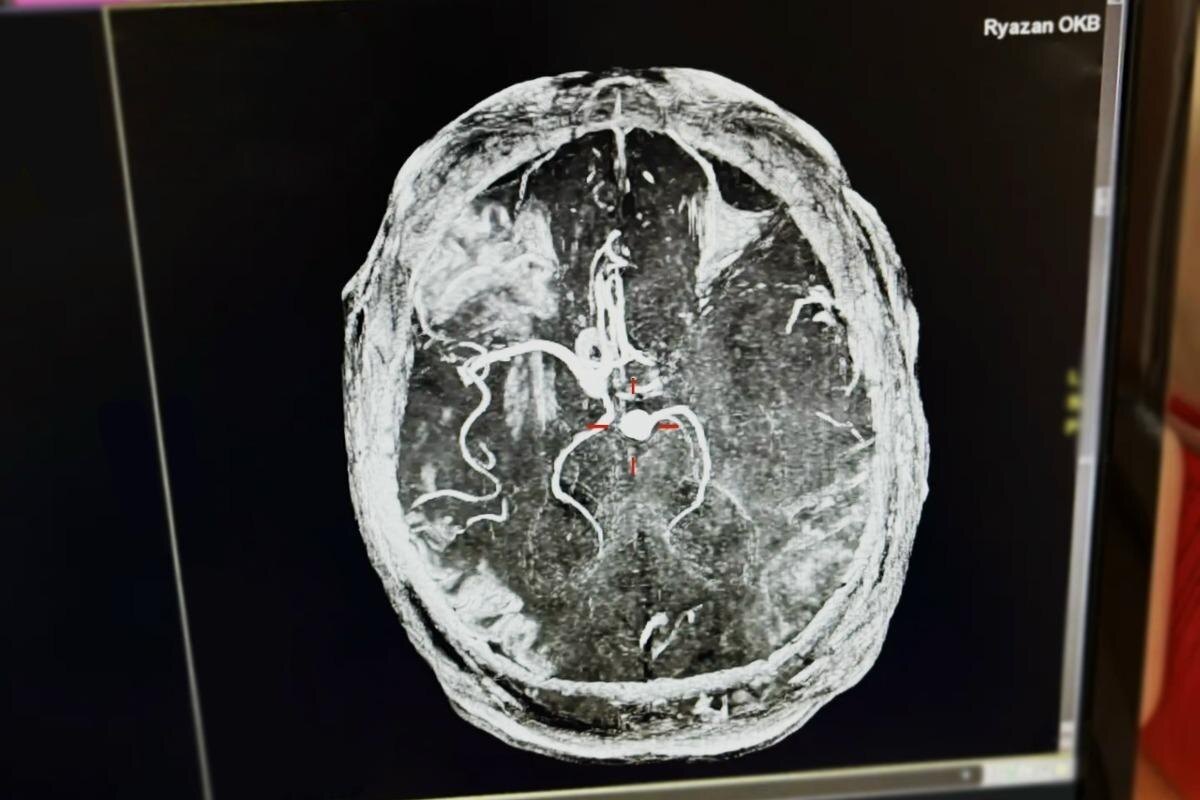

При первичном обследовании врачи зафиксировали критически высокое артериальное давление — 265 на 155 мм ртутного столба. Такой показатель указывает на тяжёлый гипертонический криз. Диагноз инсульта подтвердился после проведения необходимых исследований.

Врачи провели тромболитическую терапию, применив препараты, восстанавливающие кровоток в поражённом сосуде. Мужчина провёл в стационаре пять суток под наблюдением специалистов и был выписан в удовлетворительном состоянии.